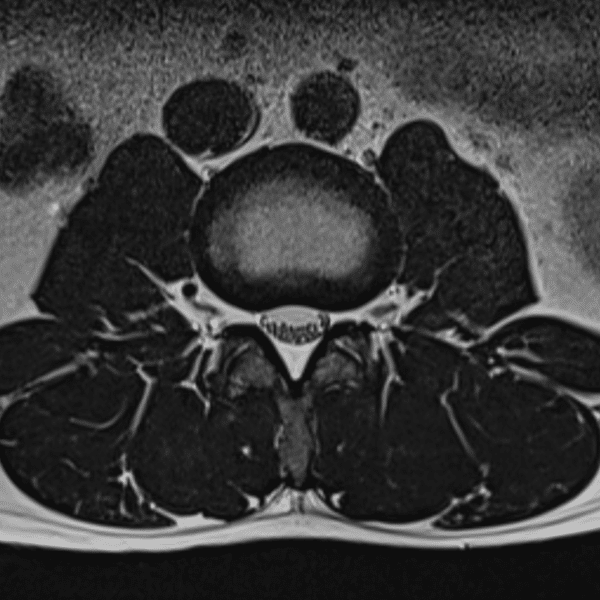

L-Spine T1WI

3.0T Philips Ingenia CX

2D TSE

(L) 0.4×0.9×3.0 mm

(R) 0.5×1.1×3.0 mm

Conventional SwiftMR™ 03:53 00:34 (85% Faster)